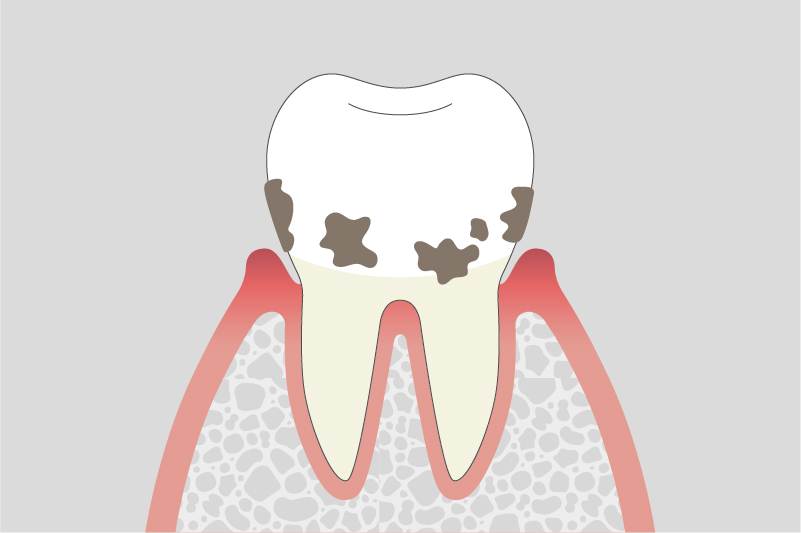

03.

中等度歯周炎

歯を支える骨(歯槽骨)が徐々に溶け始め、歯がぐらつくことがあります。また、噛んだ時に違和感や痛みを感じることがあります。